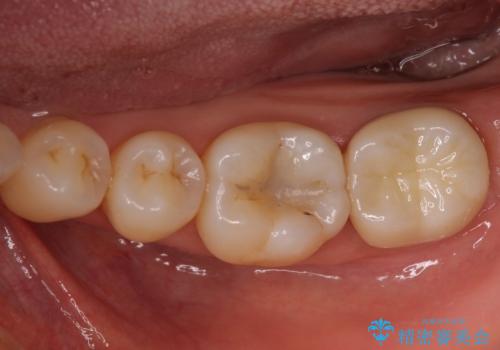

破折部位を除去したところ、外科処置が必要な深さまで破折線が及んでいなかったため、速やかにジルコニアクラウンにて補綴を行うことになりました。

神経が取り除かれた歯、特に奥歯では、歯の破折が起こりやすいので、クラウンによる補綴治療が必要であることを実感した治療でした。